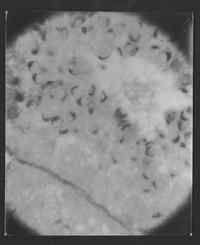

Pasta: 06354.000.136Título: Fotomicrografia de Abel SalazarAssunto: Prova microscópica de Abel Salazar, director do Instituto de Histologia e Embriologia da Faculdade de Medicina do Porto.Data: s.d.Fundo: DSZ - Documentos Abel SalazarTipo Documental: Fotografias Página(s): 1

06354.000.136

Fotografias